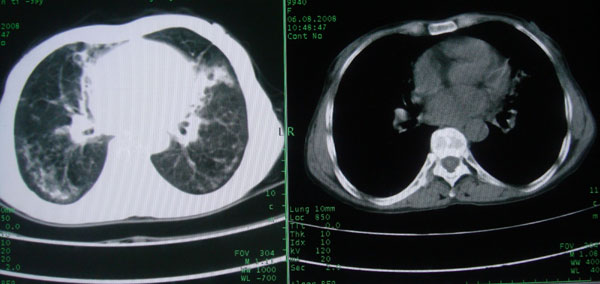

慢性支气管炎伴支气管扩张\\感染

慢性支气管病变并肺部感染。

支持慢性支气管病变并肺部感染。

肺间质性改变 支气管扩张合并感染

慢性支气管炎伴全小型肺气肿、支气管扩张、感染、间质纤维化。